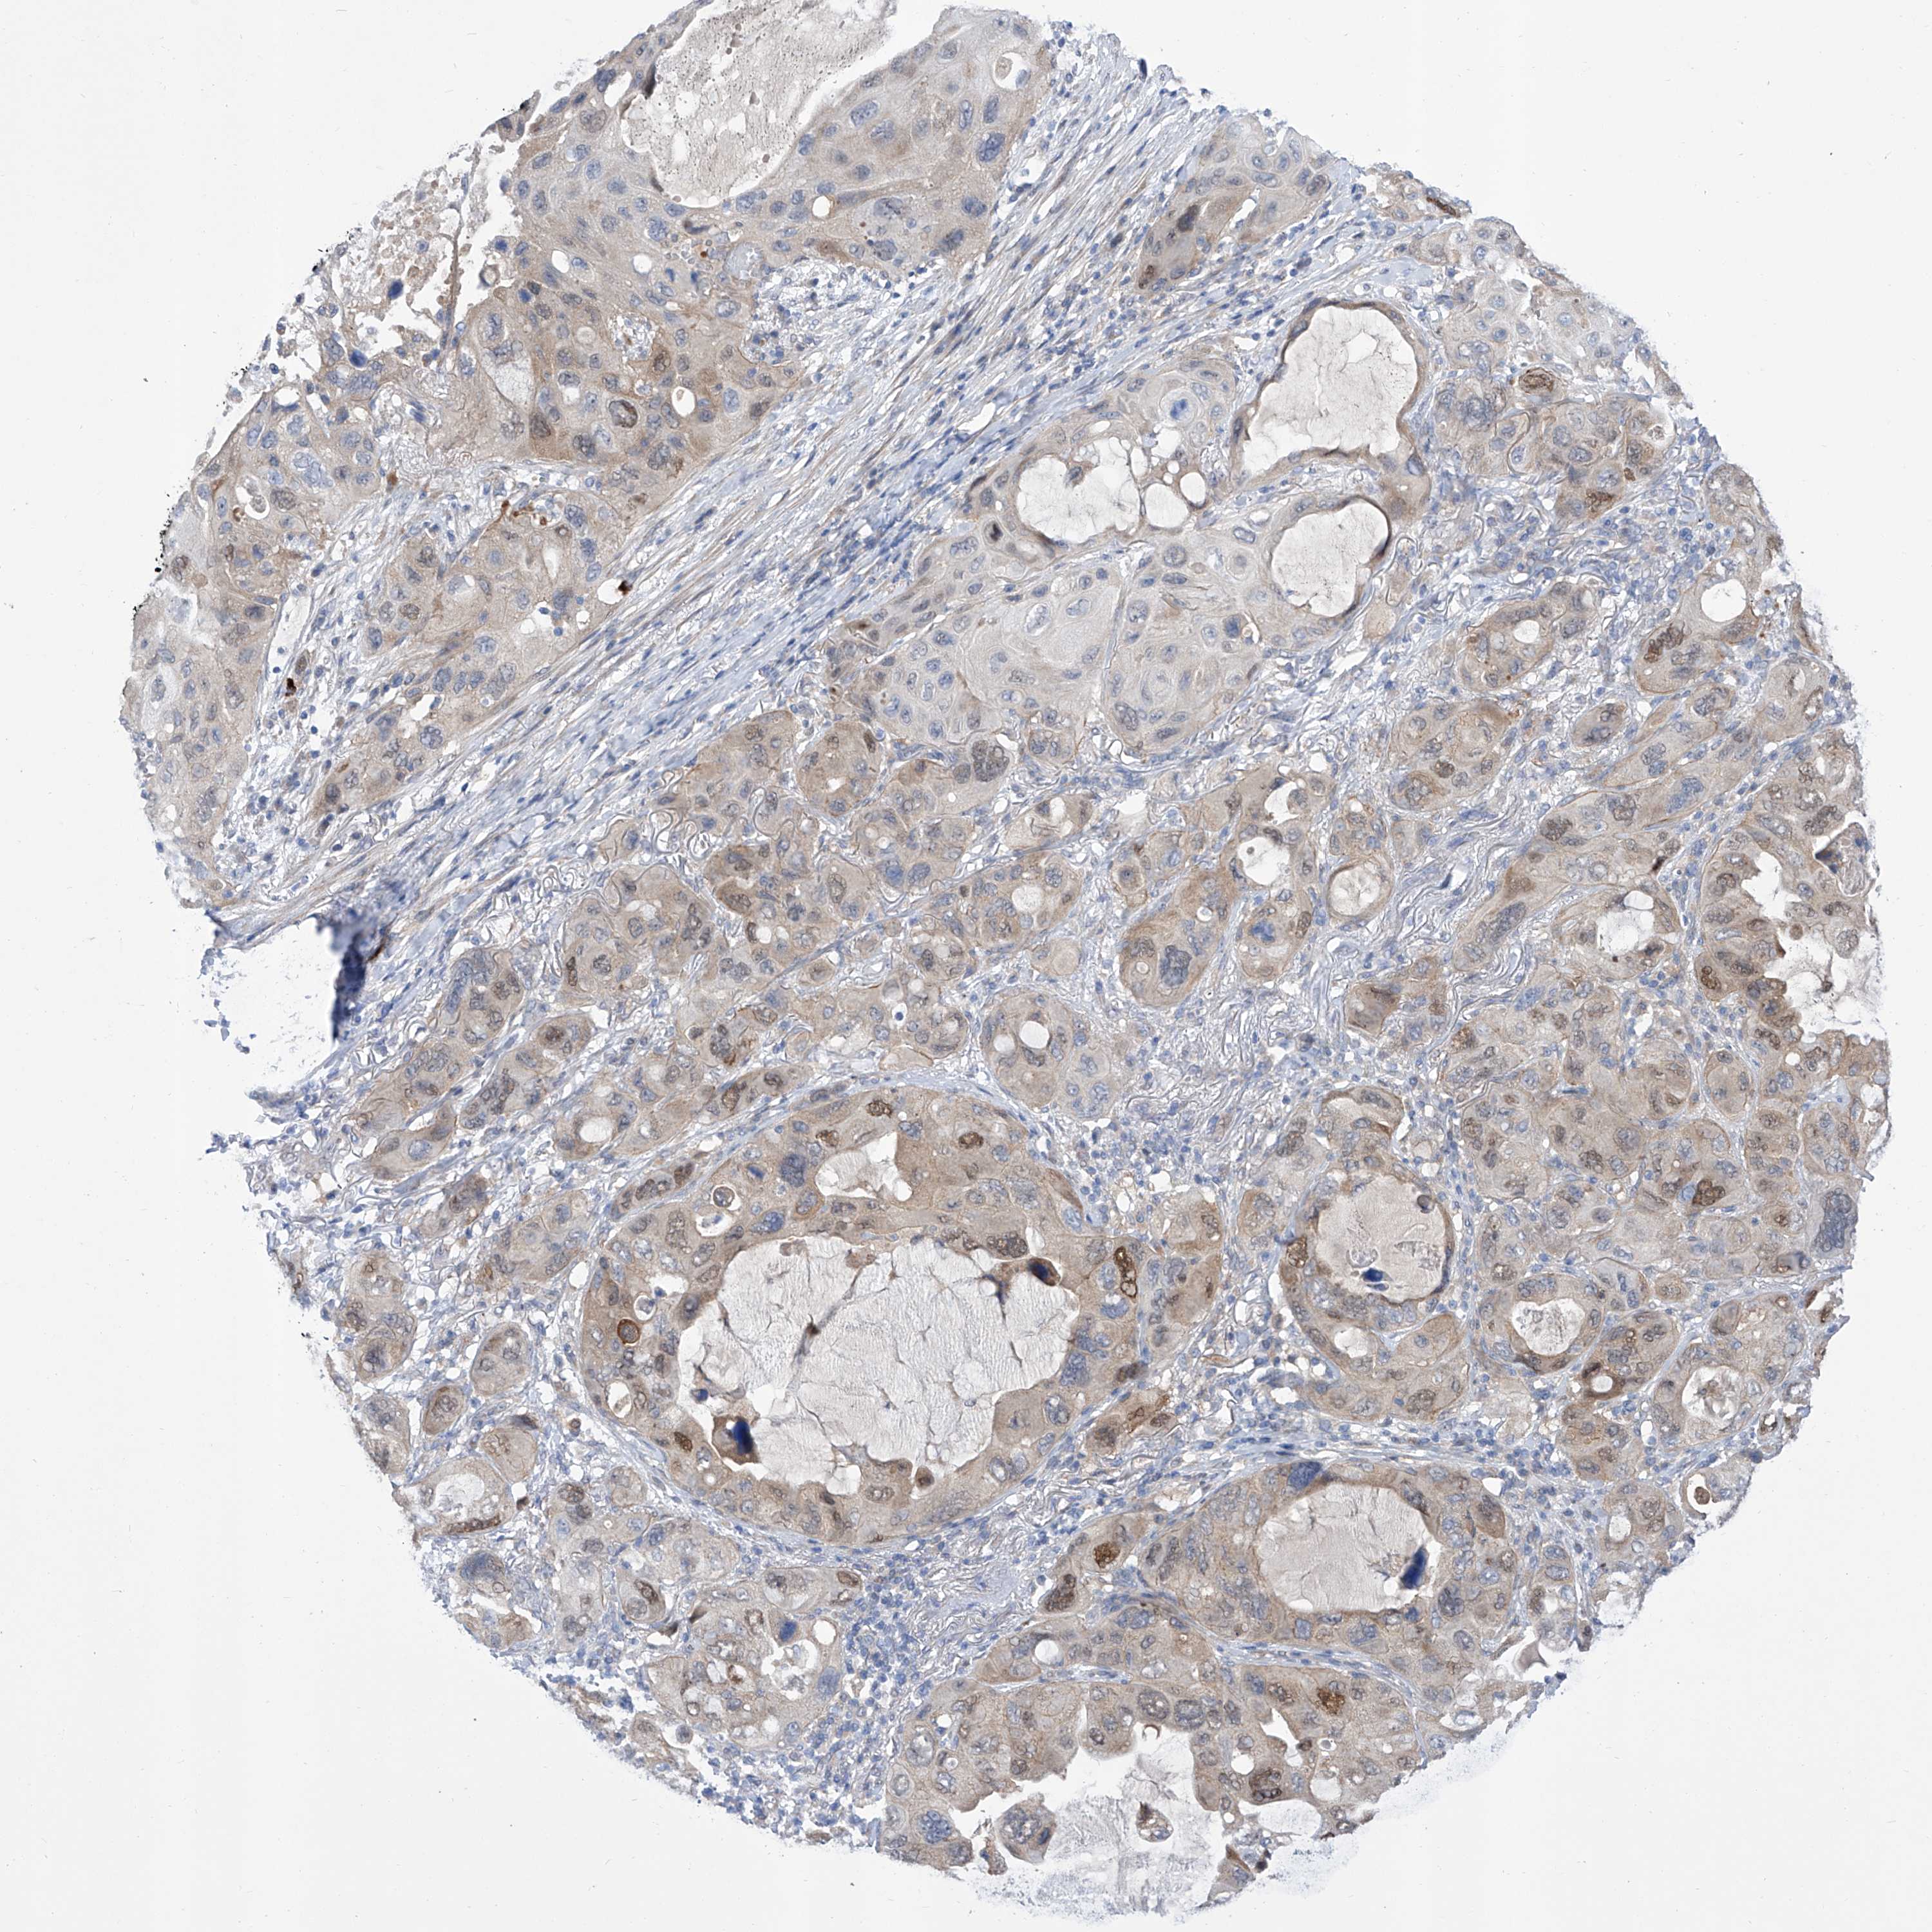

CANCER LUNG CANCER Show tissue menu

LUAD TCGA LUAD VALIDATION LUSC TCGA LUSC VALIDATION PROTEIN LUAD CPTAC PROTEIN LUSC CPTAC PROTEIN EXPRESSION

ANTIBODIES

AND

VALIDATION